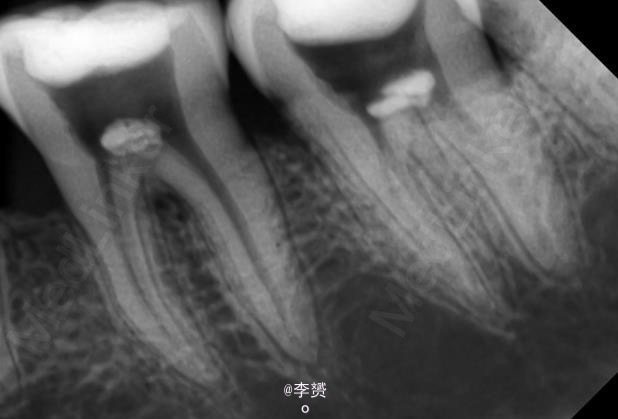

患者,女,30岁,右下第一磨牙疼痛来诊。平素体质一般,无药物、食物过敏史,无高血压、心脏病等系统病史。近期出现冷热刺激痛,根尖脓肿。

诊断 处理

在显微镜下进行断针取出